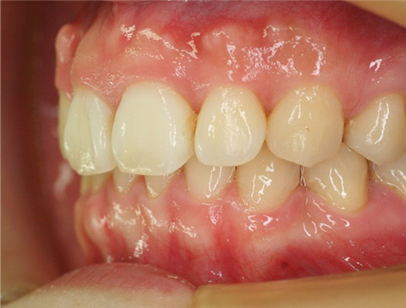

治療後

• 右側

治療前の写真と比べると上下の前歯は後方に下がりました。

そのために、鼻の下の膨らみもすっきりして、下唇も薄くなることができました。

治療期間は2年と6か月を必要としました。